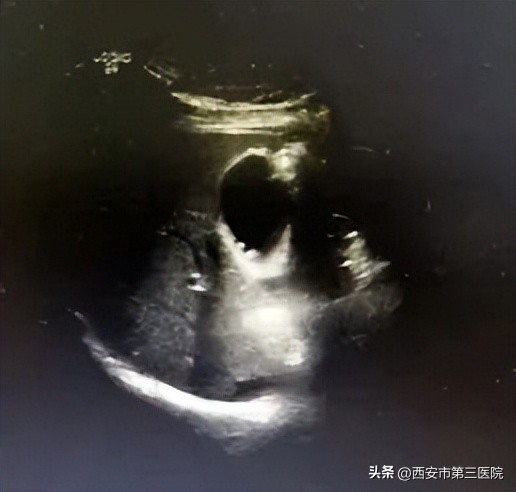

超声是胆囊息肉检查的首选方法!超声方便、快捷、检出率高、可重复检查,最重要的是超声没有辐射,对人体没有伤害。